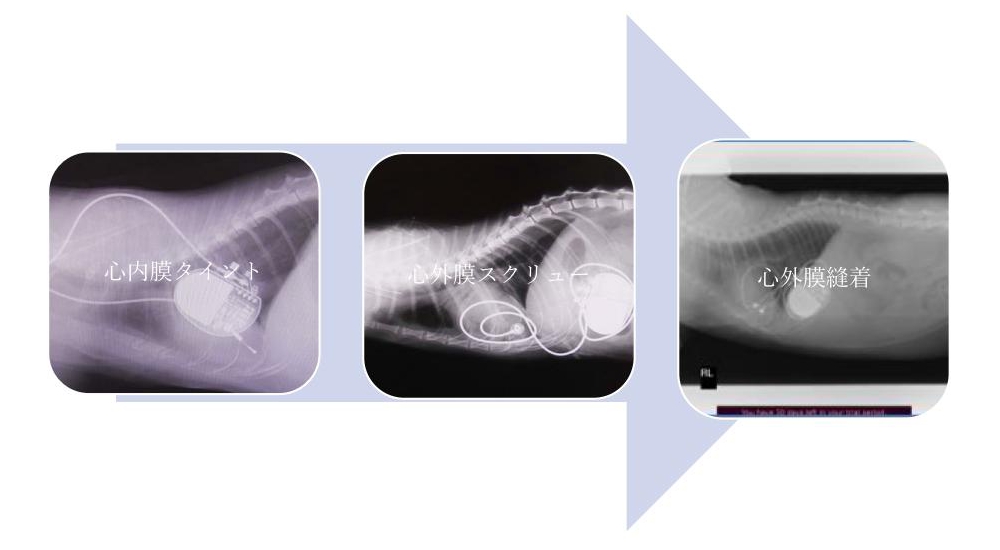

ネコの心臓ペーシング法

ネコの心臓ペーシング法としては、心内膜タイント、心外膜スクリュー、心外膜縫着を行います。